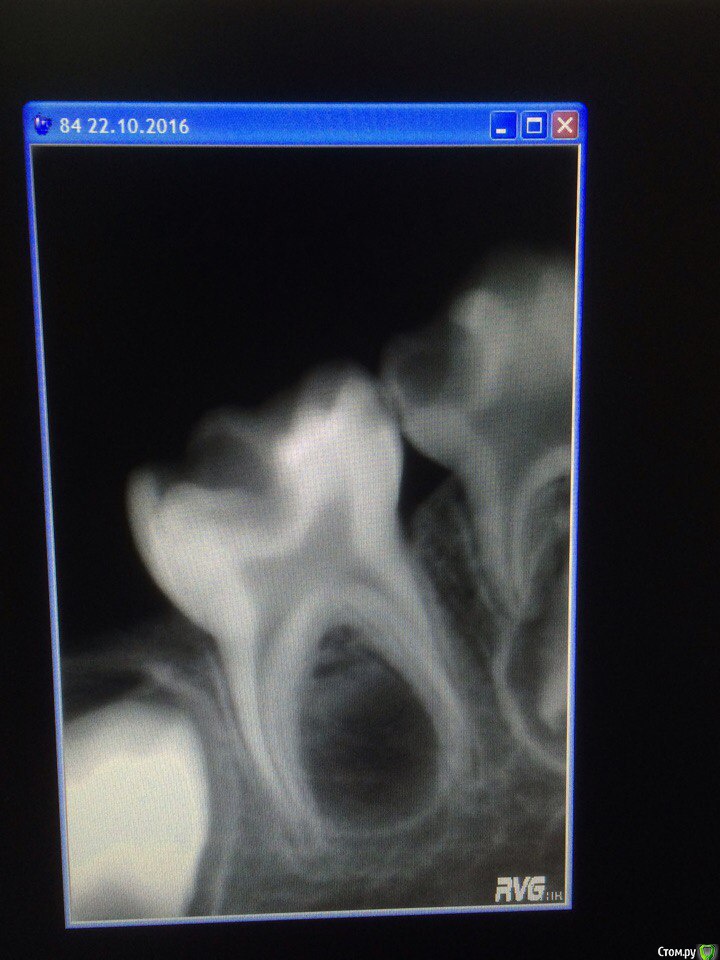

Wrestrus66 Опубликовано 22 октября, 2016 Поделиться Опубликовано 22 октября, 2016 Доброй ночи...Девочки 4 года Пришли ко мне после госки..85 зуб жалобы на ночные боли в итоге анестезию сделать не дела хотел виталку сделать !!В итоге 84,85 безмышьяк.паста...Что скажете по поводу зачатка 85?и что делать с 75зубом ??господа прошу помощи ! Ссылка на комментарий

crown Опубликовано 23 октября, 2016 Поделиться Опубликовано 23 октября, 2016 Зачатков ни под 85, ни под 75 на снимке нет. Если 75 не беспокоит, можно оставить, пока сам не выпадет. А так там совсем немного осталось до выпадения, дистальный корень только держит. Зачатка под ним нет. А че за дырень в проекции зачатка 4.5, он погиб? Ссылка на комментарий

Stom22 Опубликовано 23 октября, 2016 Поделиться Опубликовано 23 октября, 2016 (изменено) Зачатков ни под 85, ни под 75 на снимке нет. Если 75 не беспокоит, можно оставить, пока сам не выпадет. А так там совсем немного осталось до выпадения, дистальный корень только держит. Зачатка под ним нет. А че за дырень в проекции зачатка 4.5, он погиб?Я думаю, что зачаток не погиб, а его просто не было. И причём это симметрично с двух сторон. "Дырень" - это похоже на внутреннюю неравномерную резорбцию корня из-за силера может. Или же инструментальная обработка была агрессивная в каналах, стенки в корнях молочек тонкие, по кривизне можно и перепилить... Дистальный тоже неравномерно рассасывается. Изменено 23 октября, 2016 пользователем Stom22 Ссылка на комментарий

Джима Опубликовано 24 октября, 2016 Поделиться Опубликовано 24 октября, 2016 (изменено) так мой снимок постарше, кончик бугра минерализуется уже. у автора, по-моему, тоже видно контуры зачатка.а вот снимок 7.5 выглядит как раз таки так, как будто зачаток был и погиб. Изменено 24 октября, 2016 пользователем Джима Ссылка на комментарий

Джима Опубликовано 25 октября, 2016 Поделиться Опубликовано 25 октября, 2016 А как отличить погиб зачаток или изначально не заложился?Понятия не имею В книжках не попадалось. Но имеется инфа, что от Пт молочного может погибнуть зачаток постоянного. Дальше включаем голову: если на раннем этапе гибель, пока зачаток не минерализован, то это значит, по идее, что ткани фолликула вовлекаются в воспалительный процесс, и он после утихания острой фазы постепенно замещается грануляционной тканью. На снимке у автора 7.5 выглядит так, как будто острый процесс там или не был, или давно прошёл и закончился, и идёт активное продуктивное воспаление, т.е. грануляшки жрут корни и выпихивают зуб, а глубоко под зубом, ниже, тёмное пятно, в том месте, где должен был бы быть зачаток. Но кортикальной пластинки нет ( нет чёткого чёрного кружочка с белой границей), и он меньше, чем положено быть зачатку ( под 8.5 кружочек больше, если это всё-таки он). Т.е. выглядит так, как будто идёт заживление и это остатки грануляционной ткани, постепенно замещающиеся нормальной костью. Насколько я права - сложно установить, да и нужно ли? Ссылка на комментарий